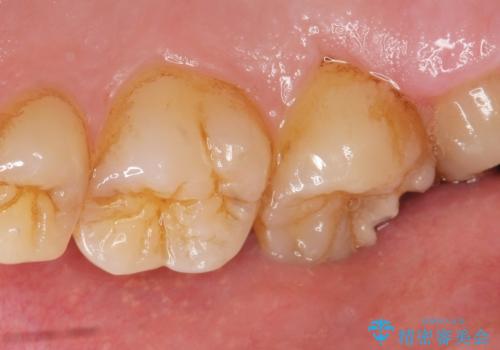

- 奥歯に食べ物がはさまることを主訴に来院された患者様です。

精査したところ、神経近くに及ぶ大きなう蝕を認めました。

神経をとらずに済むよう丁寧にう蝕を除去したのち、セラミックインレーで修復しました。